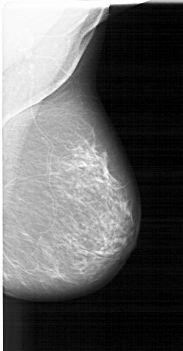

A_1410_1.LEFT_MLO

LEFT_MLO LINES 6256 PIXELS_PER_LINE 3166 BITS_PER_PIXEL 12 RESOLUTION 43.5 OVERLAY